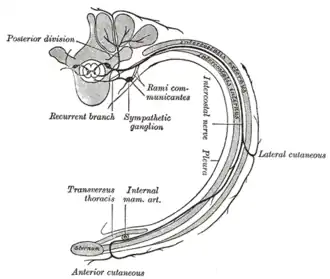

Diagram of the course and branches of a typical intercostal nerve.

Diagram of the course and branches of a typical intercostal nerve.